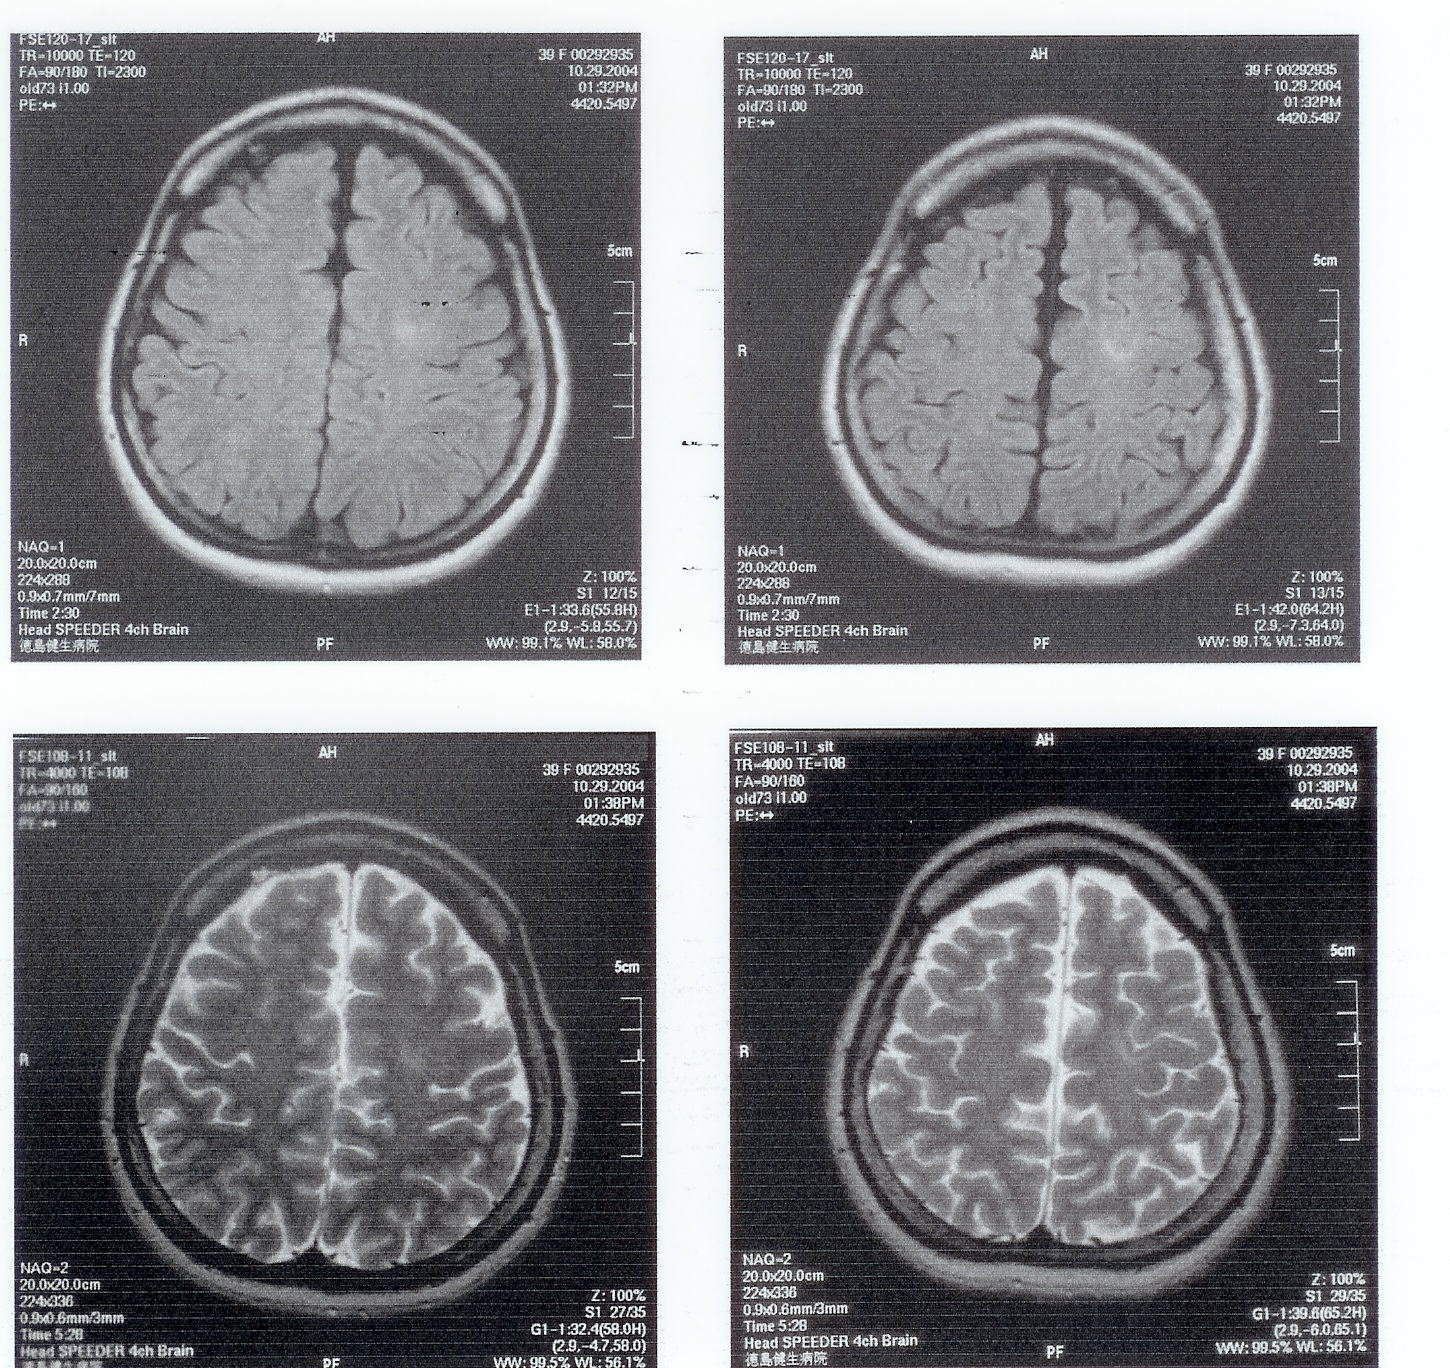

【図3-1】2003年11月25日MRI検査

一度の施術で手の痺れは良くなったものの、1月に病気の友人を見舞ったらまた悪くなり、

【図3-2】2004年1月29日MRI検査

2月1日に来院。その後、良い悪いを繰り返しながらも、

【図3-3】2004年5月27日MRI検査

【図3-4】2004年8月20日MRI検査

【図3-5】2004年10月29日MRI検査

気功を根気よく続けることで、2005年5月23日のMRI再検査では、腫瘍が消えていました。

その後は発作も起きず、手に痺れもなくなっています。

【図3-6】2005年5月23日MRI検査